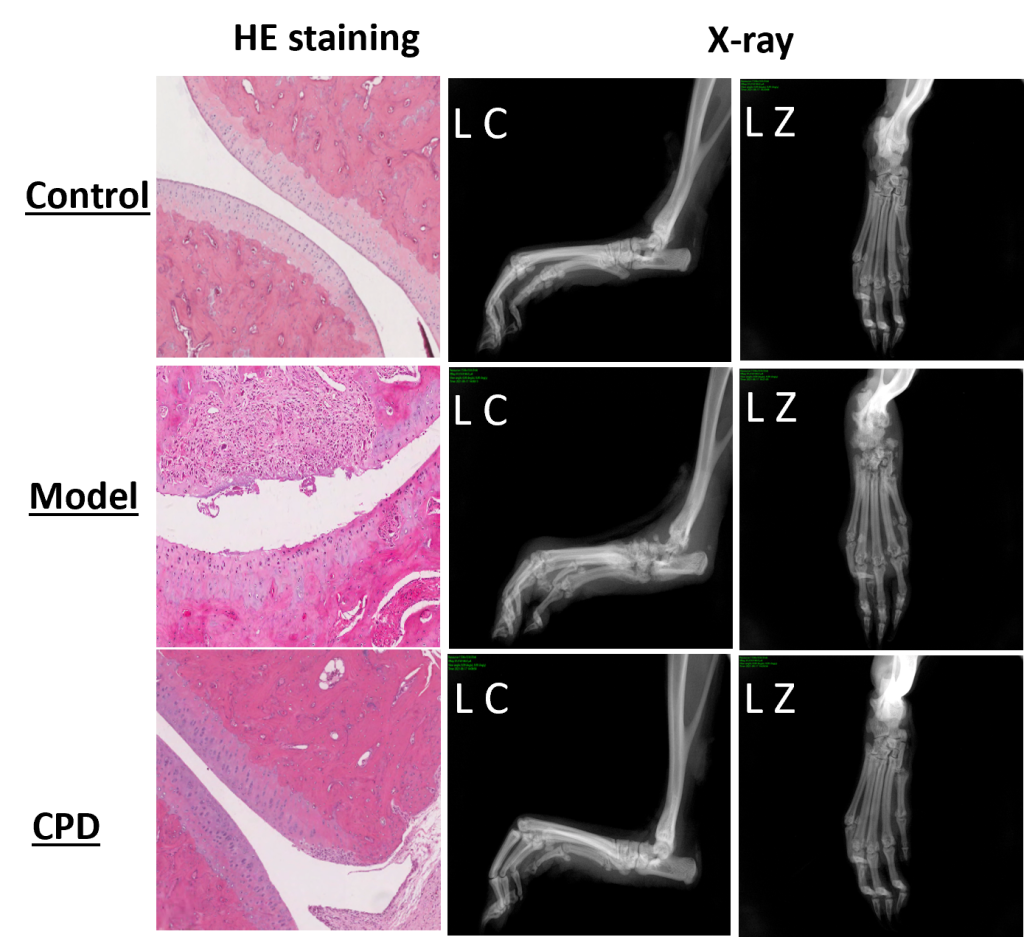

The model changes are also observable directly during the anatomical and histopathological evaluation below (CPD = tofacitinib).